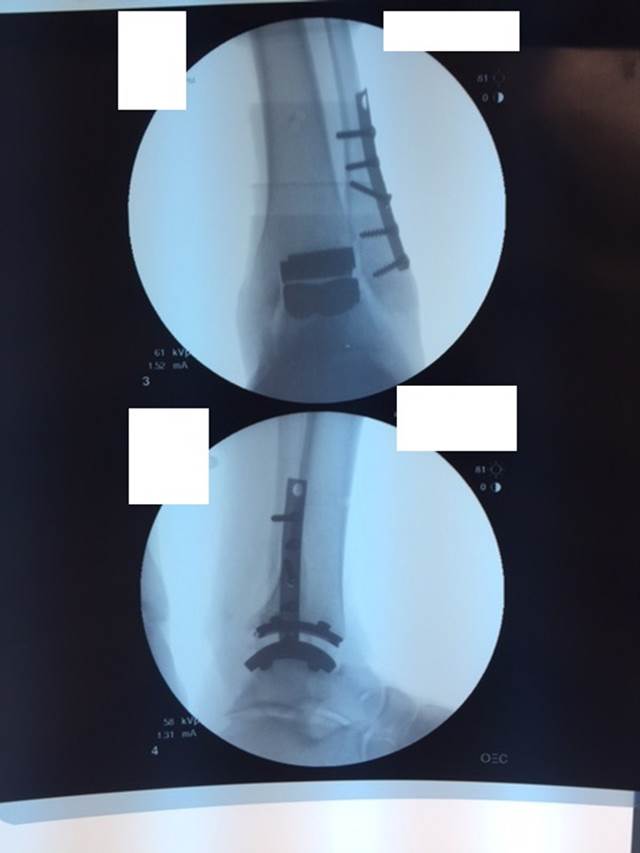

"Surgical misadventure" by another surgeon about 8 years ago. The wrong fixation was used for a flatfoot repair, & the deformity was not corrected. Patient came in with severe foot & ankle pain, with no arch at all. She was unable to play with her grandchild because the pain was so bad, & because she felt unsteady. The old hardware was removed, a lateral calcaneal lengthening osteotomy was performed along with a medial column/1st ray realignment. The ankle was painfully arthritic, & patient elected a total ankle replacement vs. an ankle fusion. She is now able to walk pain free & play with her grandchildren!